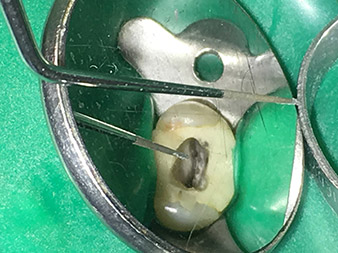

Dr. Nouraie: I particularly enjoy working with the 1E tip. It is perfectly suited to activating the rinsing fluid in the root canal system. The delicate design of the tip allows you to reach deep sections of the canal too and ensure optimal activation.

Thanks to the material reinforcement at the transition from the working end to the shaft, the risk of this thin instrument breaking has now been minimized.

Dr. Nouraie: I have various favourite tips, but my absolute favourite tip and the one I couldn’t be without is the 1E tip. It really is useful in every single root canal treatment, as it can be used to activate the rinsing fluid. It is well known that, alongside the preparation, rinsing of the root canal is the most important component of the treatment. Activated rinsing fluid penetrates deeper into the dentinal tubules, thereby achieving better results. As such, activation of the rinsing fluid plays an important role in improving the quality of this type of treatment.